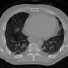

4D CT. DIR-LAB [2] thoracic image dataset for DIR that inlcudes inspiratory and expiratory breath-hold CT image pairs were used for training. Although large permutations are possible, only breathing cycles 00-50, 10-80 and 30-90 were considered from 10 different sets (a total of 120 volumes). As a consequence we avoid an imbalance in the training dataset as most of the breathing cycles did not present strong deformations. For testing the POPI [9] lung dataset was used. The provided segmentation for air, body and lungs were used for evaluation.

3.2 Registration of 4D CT data

Conv2Warp has been evaluated by comparing it to the DIR state-of-the-methods. We also provide results where we restrict the convolution blocks in the Conv2Warp model to linear convolution only (ConvNet). For both these architectures, we will compare them only for Catmull-Rom spline based interpolation as it outperformed other spline techniques in our experiments. Seven pairs of different breathing cycles of 4D-CT data [9], each with 141 slices, where improvement of DIR methods compared to pre-alignment were significant are shown in Table 1. While the accuracy of our method measured by Dice (.90) and Jaccaard coefficient (.84) is similar to the rigorous simpleElastix (SE111http://simpleelastix.github.io), the run time is reduced by a factor of 141. Conv2Warp outperforms all other state-of-the art methods and ConvNet for almost all considered pairs. The test time on CPU is nearly 2.94 s which is multiple-folds lower than conventional DIR methods. Our model is light weight with inference time on a GPU of less than 1 s.